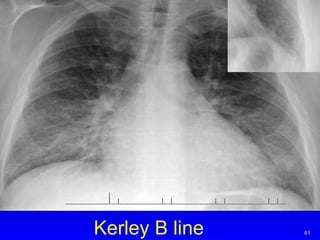

Kerley B line